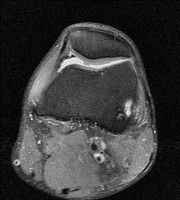

무릎 mri 간단히 봐주실 수 있으시나요 ㅠㅠ

안녕하세요 8년전 십자인대 수술하고 최근 무리한 운동에 무릎 불편감이 생겨서

mri 찍었습니다.

진단결과는 첫 찍은 병원에서 활액막염 이라는 진단을 받았습니다. 혹시 봐주실 수 있으실까요?

올라온 MRI가 단편적이라서 정확한 진단에 어려움이 있지만 십자인대에는 큰 이상이 있지는 않은것 같으며, 무릎관절내 물이 있는 것으로 보아 활액막염의 진단이 맞을 것 같습니다.

하지만 단편적인 영상이기 때문에 촬영병원에서 정확한 판독지 등을 받으시는 것이 좋겠습니다.